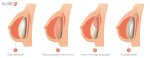

Вот хуй блеать поймешь: то ли это сиськи натурально разъехались, то ли это импланты.

Мне хочется сказать, что у неё мышечные импланты, но сомневаюсь.

Нет у нее имплантов.

Это уже птоз.

И там консервативными методами уже не отделаться...